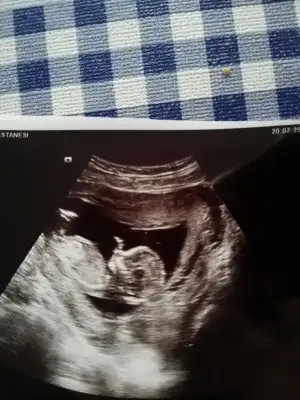

Evet regl dönem bakınca 8 hafta doktor 9+3 dedi.

Teşekkürler bu ay sonu gibi çağırdı doktor 2.tarama yapıcak tekrar alırım ultrason buraya yüklerim.

13 hafta ya girmiş olucaz daha net olur o zaman çok teşekkür ederim sağolun